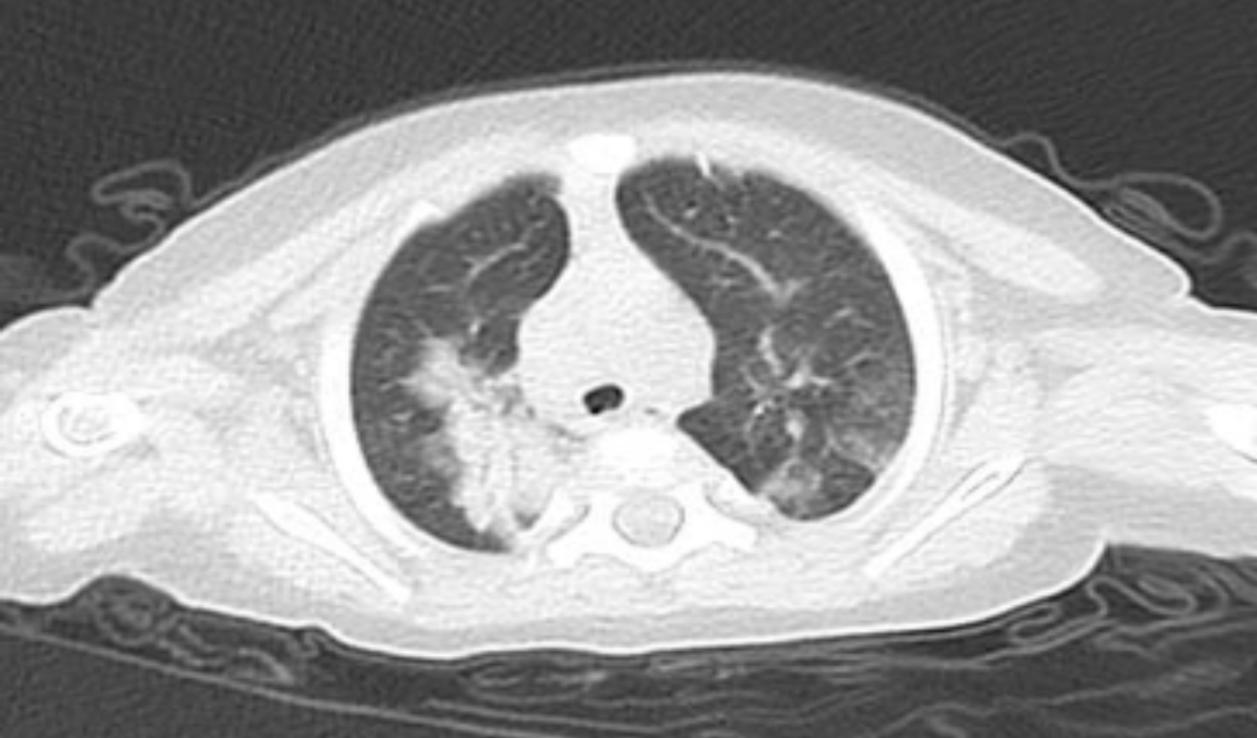

胸部CT提示:雙肺多發(fā)炎癥并實(shí)變